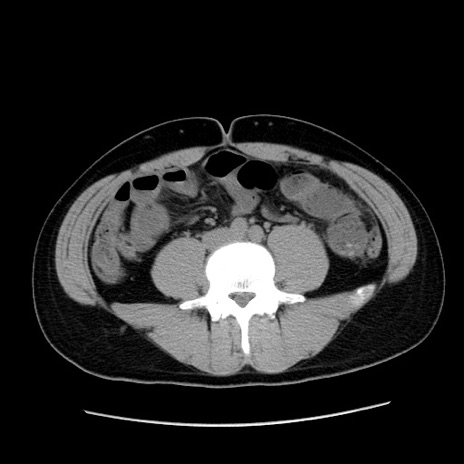

冠状断像

症例36(横断像)

【症例】20歳代 男性

【主訴】心窩部痛

【現病歴】今朝より上腹部痛あり。一旦軽快していたが再度出現したため救急要請。昨日夕に白身の魚を含む刺身を食べた。

【身体所見】BP 136/89mmHg、HR 74/min、BT 37.0℃、腹部:膨満、軟、心窩部に圧痛あり。反跳痛なし、筋性防御なし、腸雑音やや亢進あり。

【データ】WBC 17700、CRP 0.48